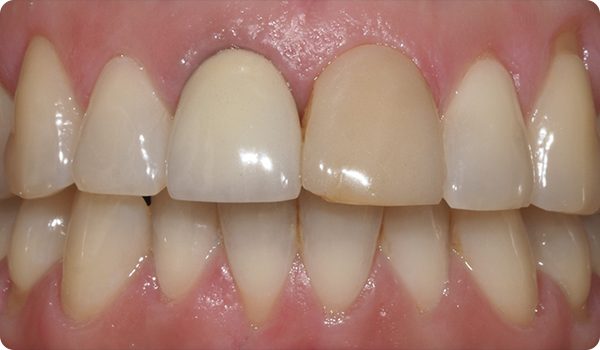

Het uitlijnen van de tanden met Right is de perfecte en meest conservatieve basis voor toekomstige whitening of fineerbehandelingen die de glimlach van de patiënt perfect maken.